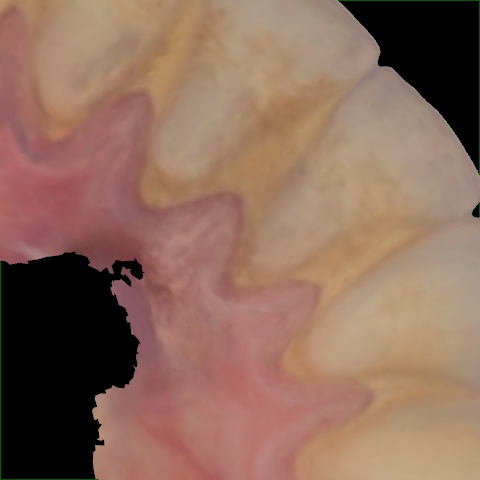

Image 134 / 1527

NHD39455

Annotated as "Good"

Original Image Rendering Image